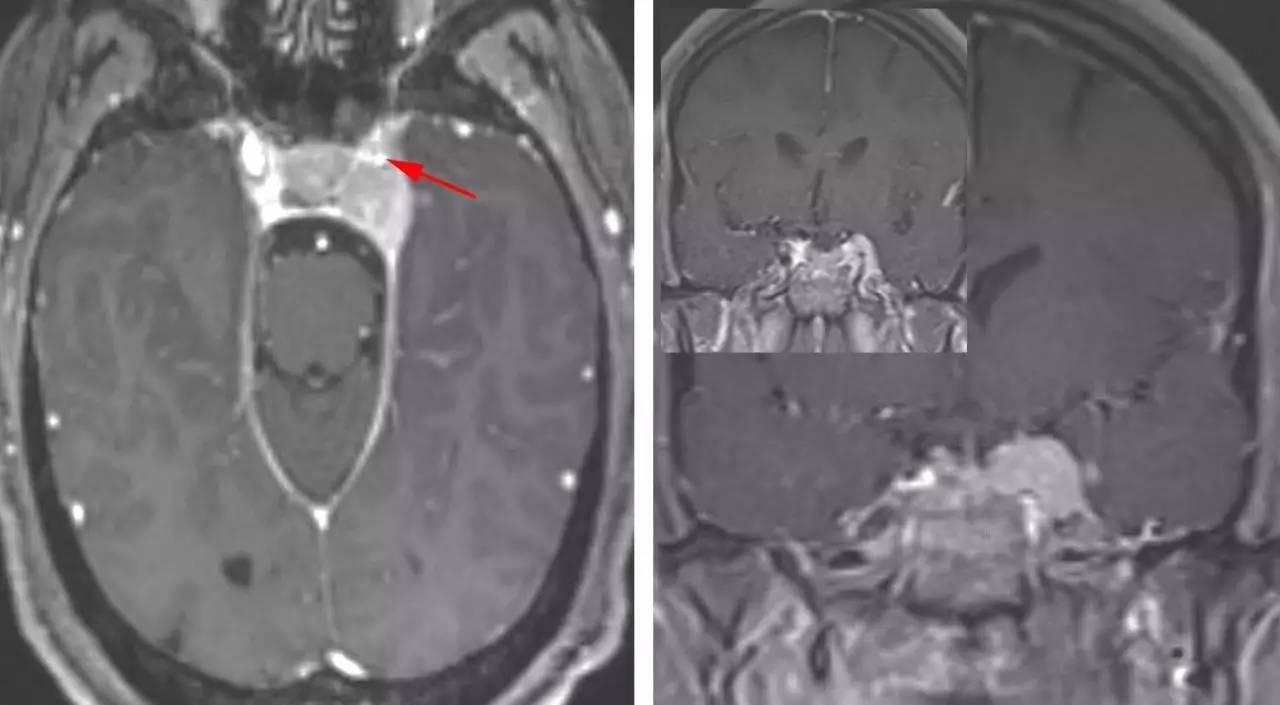

图1:一例较小的左侧海绵窦脑膜瘤。可见海绵窦段颈内动脉被肿瘤包裹并管腔狭窄(箭头),提示应避免对动脉的过度操作。该占位向外推挤海绵窦外侧硬膜缘。沿天幕游离缘可见明显的脑膜尾征。